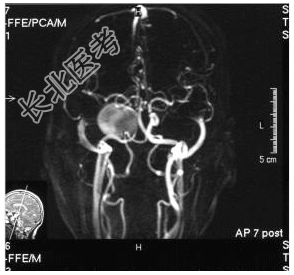

- [材料题] 患者,女性,59岁,因复视、右面瘫及蚁行感半年,间有头疼,无呕吐入院。体检:神清,右外展不全,复视,右面部皮肤感觉尚好,伸舌居中,右指鼻试验(-),四肢(-)。做头颅MRI检查。

- 简答题1、请问诊断是什么?

- 简答题2、诊断依据是什么?

- 简答题3、鉴别诊断有哪些?